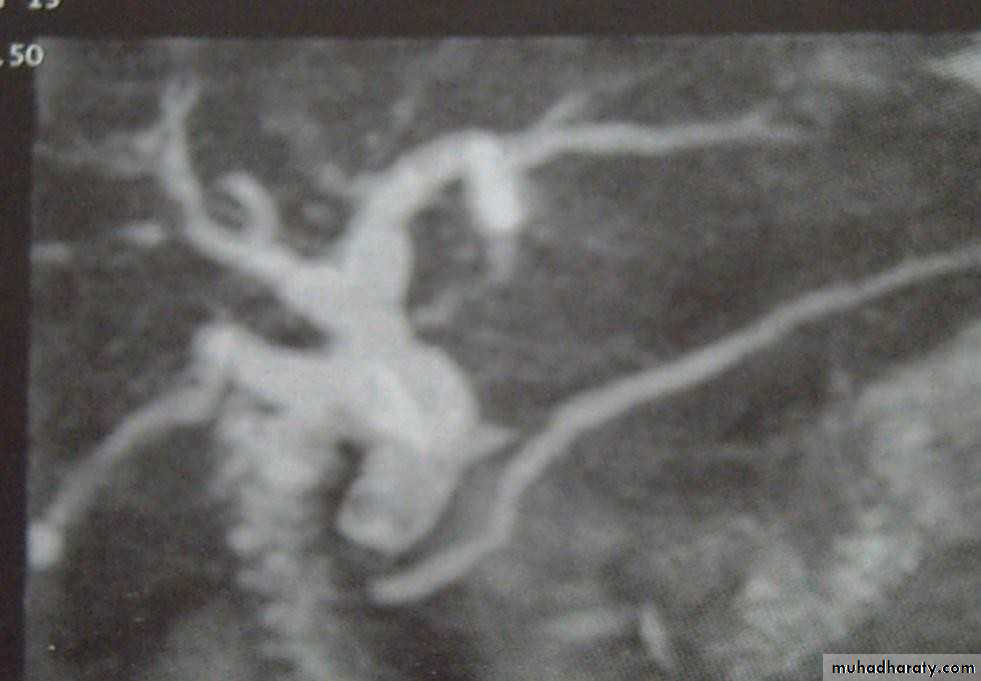

• MRCP

• Magnetic resonance cholangio- pancreatography crosssectional

• image demonstrating a hilar mass (thick• arrow) and gallstones (thin arrow)